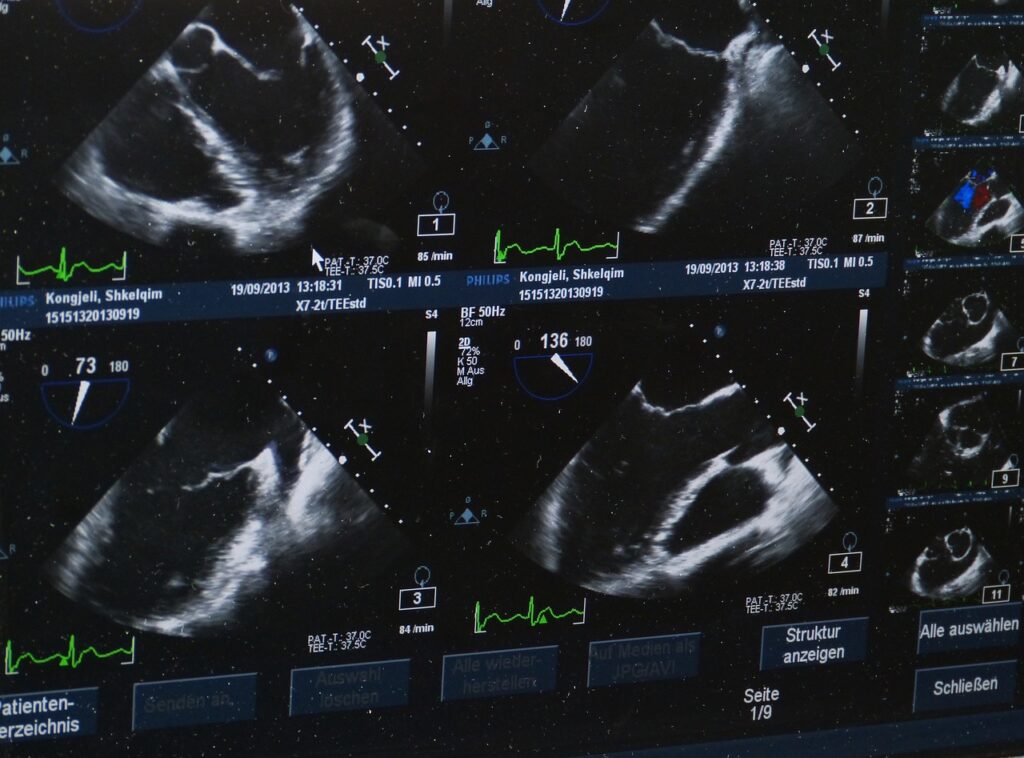

Les échographies utilisent des ondes ultrasonores, une forme de son qui ne peut être entendue par l’oreille humaine, pour créer des images des organes du corps. Le rôle de ces ondes est crucial. En passant à travers le corps, elles rebondissent sur les tissus et les organes, créant des échos qui sont captés par la sonde.

La technologie repose sur le principe du sonar, utilisé initialement pour la navigation en mer. Une fois retranscrits en images, ces échos permettent de visualiser les structures internes, offrant ainsi aux médecins un outil précieux pour le diagnostic sans avoir à recourir à des procédures invasives. Les transducteurs, également appelés sondes, convertissent ces échos en images sur un écran, permettant une visualisation directe et rapide des structures internes. De plus, l’application de gel sur la peau améliore la transmission des ultrasons, minimisant ainsi la réflexion de l’air qui pourrait perturber la qualité de l’image.